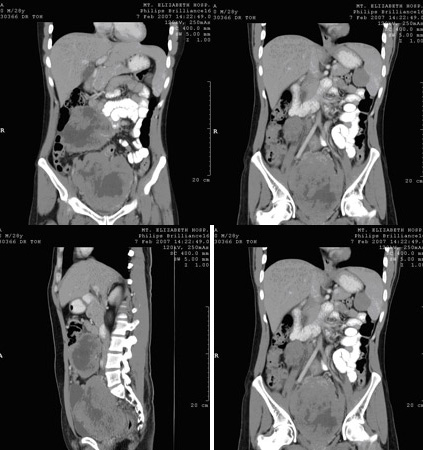

Six weeks of chemo and radiotherapy shrunk the mass completely. After 6 weeks, no residual cancer was felt on rectal examination. Further X rays showed spread elsewhere and Mr Chia was advised for rectal surgery. An ultra-low anterior resection was done on Oct 2006. Histological examination of the resected specimen showed complete clearance of cancer. Mr Chia is expected to have a good prognosis.